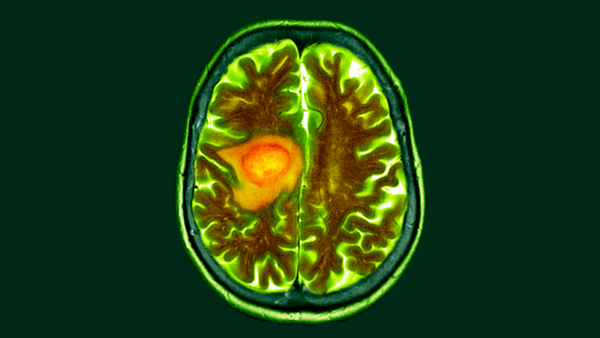

Старіючі клітини іноді називають «зомбі-клітинами», бо вони, своєрідно, нежить. Клітини перестають ділитися через стрес або пошкодження, але залишаються в організмі та спричиняють проблеми в контексті старіння. (Зображення: OsakaWayne Studios via Getty Images)